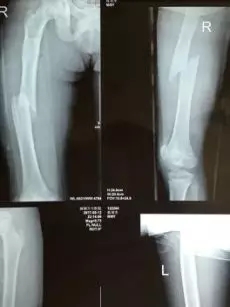

因是晚上又是急诊,深圳万丰医院为他立即进行了DR检查,经诊疗专家商讨后诊断:为右侧股骨中段骨折。

他为什么这么容易就骨折了?当时负责给小桂治疗的骨科主任雷光华主任医生的判断是:“该小孩并不是普通的摔伤,而是骨头中间长了肿瘤,为骨纤维异样增质症,是股骨肿瘤(良性)引起的病理性骨折,需要进行肿瘤病灶清除手术才能治疗康复。”

▲小桂手术X线片前后对比图